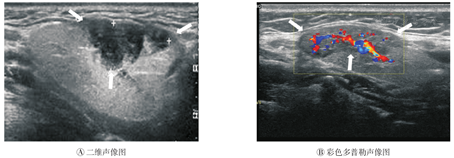

局限性结节样改变,共2例2灶(9.1%)。病侧腺体大小(长径×厚径)分别为2.4 cm×1.4 cm和3.6 cm×1.8 cm。病侧腺体内显示低回声区,大小分别为2.6 cm×0.8 cm和2.3 cm×0.9 cm;位于腺体的浅侧、被膜下,1例向外隆起;低回声区不均匀增粗(图2A),内见条状强回声,边界模糊,后方回声增强,内血流偏多(图2B),无明显占位效应。未累及区呈正常颌下腺超声表现。